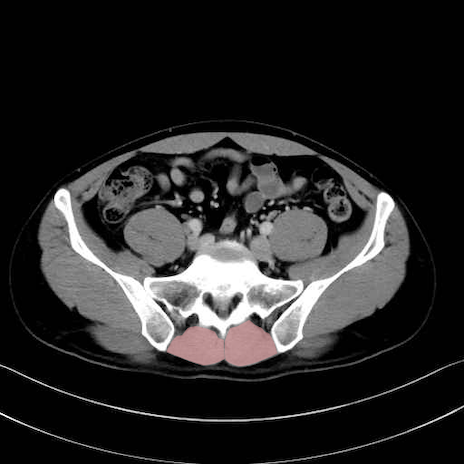

肛門挙筋 (Levator ani)